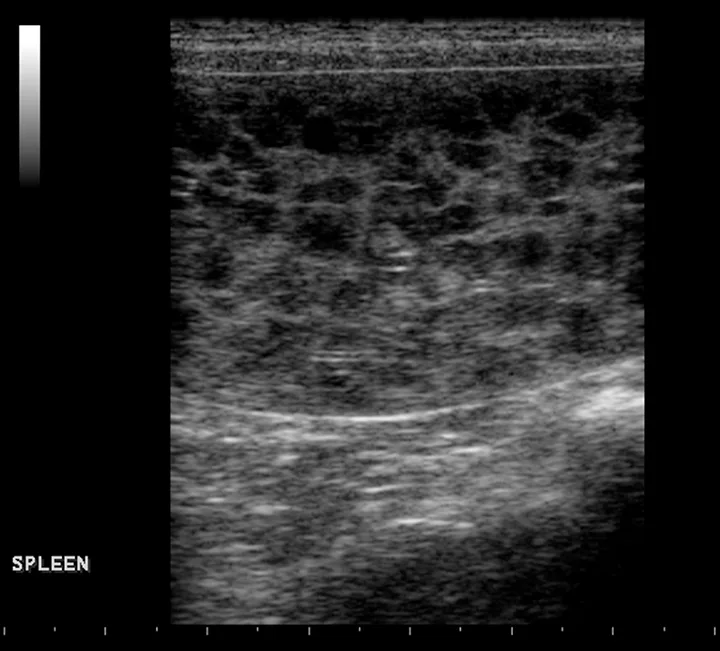

Lymphoma is a systemic disorder of uncontrolled proliferation of neoplastic lymphoid cells. Multicentric lymphoma is the most common form of lymphoma in dogs, and the liver and/or spleen are frequently involved (Stage IV).12 Infiltration of neoplastic lymphoid cells often causes a diffuse enlargement of the spleen that results in a characteristic “honeycomb” or “moth-eaten” appearance on ultrasonography (Figure 3),13 which has a sensitivity of 100%, specificity of 23.3%, positive predictive value of 64.7%, negative predictive value of 100%, and accuracy of 68.1% for diagnosis of splenic lymphoma.13

Featured Image

FIGURE 3

Numerous, variably sized, sharply defined, hypoechoic nodules with a “honeycomb-like” appearance are characteristic of splenic lymphoma.

In one study, fine-needle splenic aspirate findings confirmed lymphoma in all multicentric lymphoma patients with a moth-eaten appearance of the spleen.13 Further differentiating lymphoma type (B-cell vs T-cell) using flow cytometry helps with prognosis. Treatment with chemotherapy is considered standard of care and is associated with 80% to 90% remission rates with median survival times of 10 to 12 months, depending on the chemotherapy protocol used.12